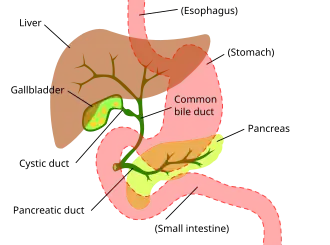

Cholangiocarcinoma can affect any area of the bile ducts, either within or outside the liver. Tumors occurring in the bile ducts within the liver are referred to as intrahepatic, those occurring in the ducts outside the liver are extrahepatic, and tumors occurring at the site where the bile ducts exit the liver may be referred to as perihilar. A cholangiocarcinoma occurring at the junction where the left and right hepatic ducts meet to form the common hepatic duct may be referred to eponymously as a Klatskin tumor.[40]

While abdominal imaging can be useful in the diagnosis of cholangiocarcinoma, direct imaging of the bile ducts is often necessary. Endoscopic retrograde cholangiopancreatography (ERCP), an endoscopic procedure performed by a gastroenterologist or specially trained surgeon, has been widely used for this purpose. Although ERCP is an invasive procedure with attendant risks, its advantages include the ability to obtain biopsies and to place stents or perform other interventions to relieve biliary obstruction.[12] Endoscopic ultrasound can also be performed at the time of ERCP and may increase the accuracy of the biopsy and yield information on lymph node invasion and operability.[56] As an alternative to ERCP, percutaneous transhepatic cholangiography (PTC) may be utilized. Magnetic resonance cholangiopancreatography (MRCP) is a non-invasive alternative to ERCP.[57][58][59] Some authors have suggested that MRCP should supplant ERCP in the diagnosis of biliary cancers, as it may more accurately define the tumor and avoids the risks of ERCP.[60][61][62]